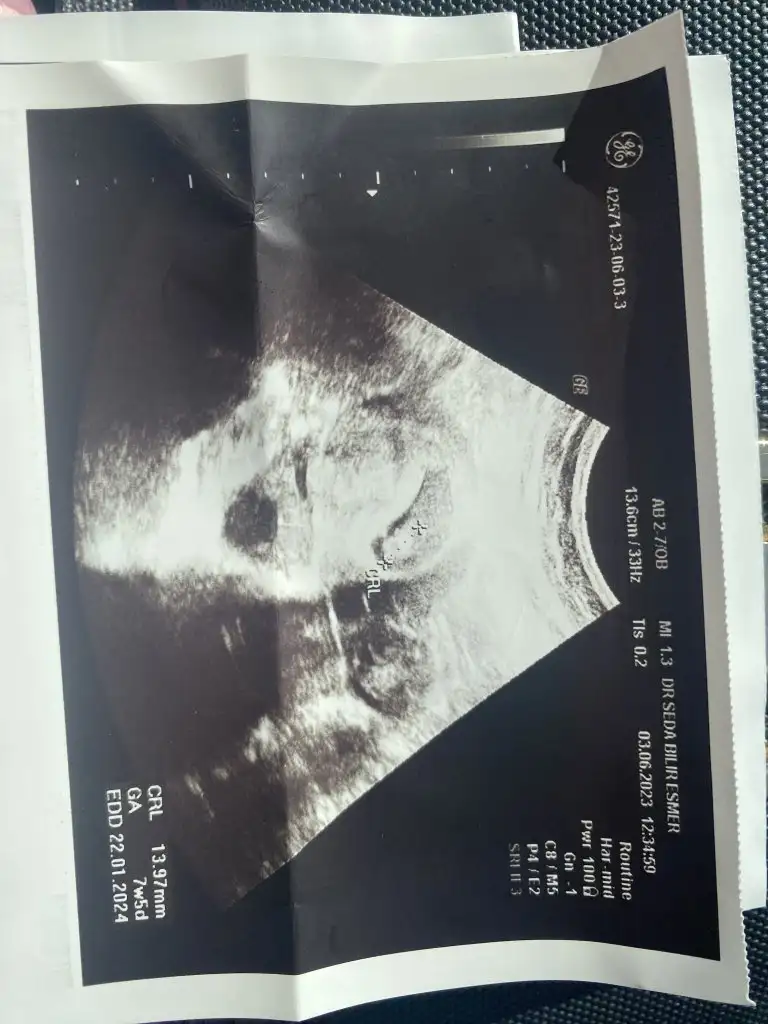

Selam kızlar. Ben de 7+4 oldum çok şükür. Dün kalp atışını gördük. Bugün böyle afedersiniz sümükümsü bir akıntım var. Yaşayan oldu mu hiç. Normal mi acaba. Netten biraz araştrdım da normal yazıyor. Özellikle adet dönemlerine denk gelen zamanlarda oluyormuş. Hesapladım da benm de adet dönemime denk geliyor